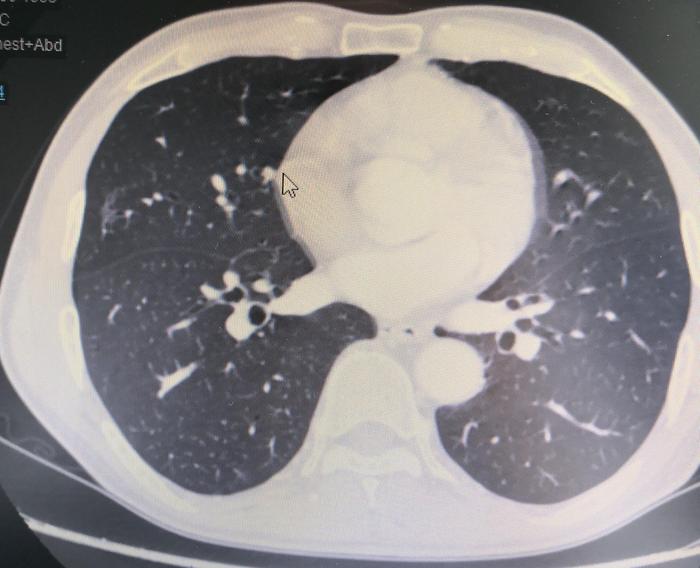

上图(图7),我们医院和扬州一样没有看到这个磨玻璃结节。